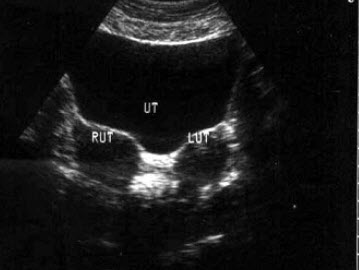

61、单项选择题

宫底呈“羊角形”,两角内可见分叶状宫腔线,宫体下段及宫颈形态正常。该超声图像是指()

A.双子宫

B.残角子宫

C.双角子宫

D.纵隔子宫

E.以上均是